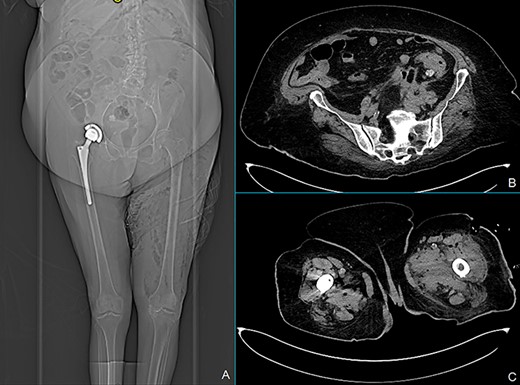

Total body X-ray shows marked left leg emphysema (A). CT scan of the lower abdomen showing covered posterior sigmoid perforation, sigmoid thickening and retroperitoneal collections (B). Marked air and fluid collections in medial and anterolateral compartment of the left leg at the CT scan (C).

We report a case of a 71-year-old woman with Class 3 obesity and Type 2 diabetes. The patient initially came to the emergency room for abdominal pain, fever (38.5°C) and swelling of the left lower limb. The blood tests showed a neutrophilic leukocytosis with white blood cells (WBC) 15 700 cells/mmc, neutrophils 13 800 cells/mmc, C-reactive protein (CRP) 303 mg/l and serum glucose 275 mg/dl. At the physical examination, the abdomen was soft with lower left quadrant tenderness, and the left lower limb was painful and warm with marked edema starting from the inguinal region. The patient was hemodynamically stable. Computed tomography (CT) scan of the abdomen extended to the lower limbs (Fig. 1) revealed the presence of air and fluid retroperitoneal collections, extending through the posterior abdominal wall muscles until the medial and anterolateral compartment of the left leg. Besides, thickening of the sigmoid wall with covered perforation was detected. Clinical and radiological findings were consistent with extensive gangrenous fasciitis possibly secondary to perforated diverticulitis. Wide-spectrum antibiotic therapy with meropenem and vancomycin was started and urgent fasciotomies were performed on the anterior, medial and lateral sides of the left leg. The patient was also treated with hyperbaric oxygen therapy and referred to the intensive care unit (ICU). A cultural test showed a polymicrobial infection of Klebsiella pneumoniae, Enterococcus faecalis and Candida albicans. Blood cultures were positives for Staphylococcus epidermidis. According to these findings, the antibiotic therapy was implemented by adding fluconazole and the hyperbaric therapy was stopped. The first postoperative course was uneventful. In postoperative Day (POD) 8, a CT scan showed a reduction of collections both in the retroperitoneum and in the left leg prompting the discharge of the patient from ICU. At that moment, we decided not to treat the diverticulitis surgically, according to the recent Consensus Statement of the European Association for Endoscopic Surgery and Society of American Gastrointestinal and Endoscopic Surgeons. In POD 16, since blood tests were completely normalized, physical examination of the abdomen was negative and surgical incisions were dry and clean, the patient was transferred to the rehabilitation unit. After 37 days from surgery, the patient was readmitted to our unit because of the occurrence of fever and the formation of a fistula at the site of the lateral fasciotomy producing fecal material (Fig. 2). The CT scan revealed marked improvement of abdominal and limb conditions, with a reduction of the pericolic abscess, collections and edema of the left leg (Fig. 3). Lab tests showed WBC 7800 cells/mmc, CRP 183 mg/l. Although CT scan findings showed improvement, the clinical evidence of colocutaneous fistula prompted us to surgery. Intraoperative findings confirmed acute diverticulitis with posterior covered perforation and retroperitoneal fistula. An enterocolic fistula was also detected. There was no contamination of the peritoneal cavity; so we performed sigmoid resection with primary mechanical end-to-end anastomoses without proximal diversion and ileal loop repair. Two drain tubes were placed both in the abdominal cavity and through the lateral fasciotomy. No early or late severe postoperative surgical complications were observed. In POD 4, the patient returned to normal bowel function and started oral refeeding. Abdominal and left leg drain tubes were respectively removed in PODs 5 and 7. An episode of fever (39.3°C) occurred in POD 9 and was attributed to candida infection and treated with antifungal therapy and central venous catheter removal. In POD 27, the patient was finally discharged in good clinical condition with normal lab tests and left leg wound re-epithelialization.